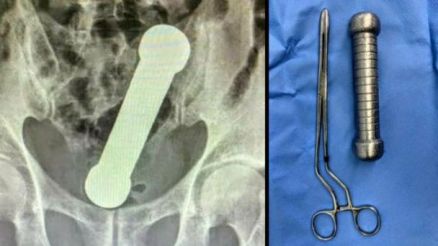

Médicos encontraram um peso de dois quilos, e cerca de 20 centímetros de comprimento dentro de um homem de 54 anos, em Manaus.

O peso é dos mesmos usados em academias de ginástica para exercícios de braço. O fato inusitado rendeu um relato de caso publicado na plataforma científica International Journal of Surgery Case Reports na última quarta-feira (6).

O paciente procurou o serviço médico reclamando de dores de estômago, náuseas e dificuldade de evacuação, sintomas que persistiam há dois dias. Porém, ele não forneceu detalhes sobre o que poderia ter causado a condição.Raio-X detectou o peso dentro do homem.

Ao realizarem um exame de raio-X, os médicos encontraram um peso, dentro do homem.

Segundo as imagens, o haltere estava entre o reto e o intestino grosso do paciente, que, depois do exame, admitiu ter introduzido o peso de academia no corpo para obter satisfação sexual.Para retirar o objeto, a equipe médica sedou o homem.

Inicialmente, os médicos tentaram puxar com uma pinça cirúrgica, mas como não foi possível, a retirada teve de ser feita por um dos cirurgiões com as mãos.